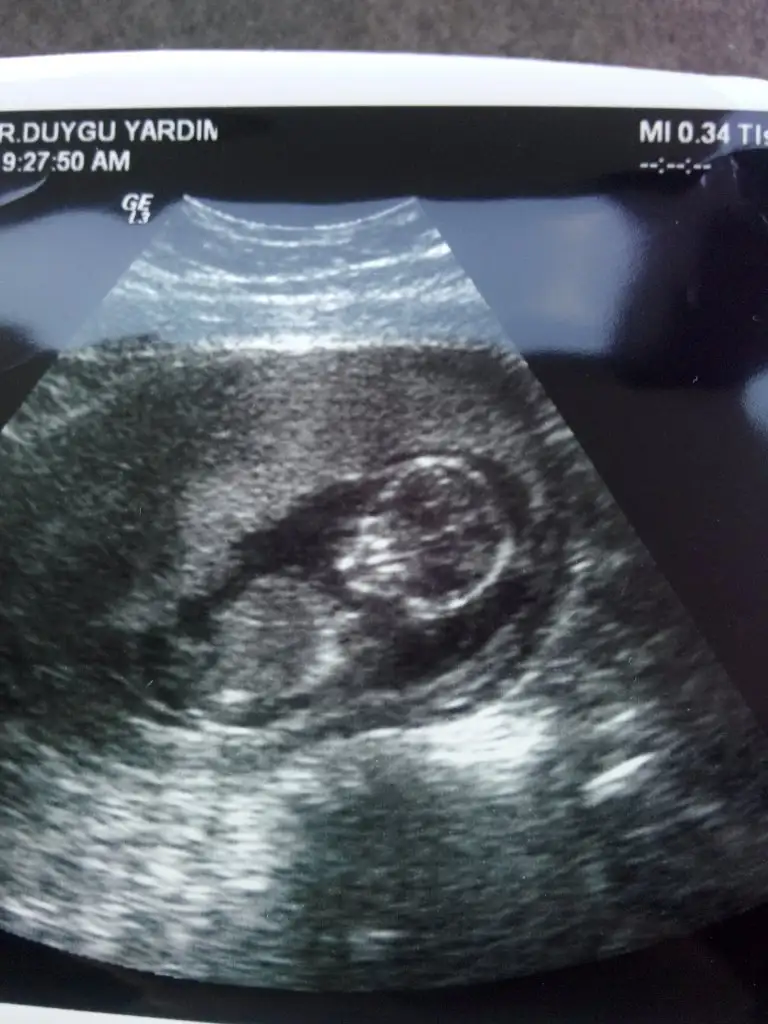

dr soylemeden siz gorun genital nub teorisi ( bebegin cinsiyeti)

Kizlar benim bebegimede yorum yapin çok rica edyrm .12+5 im burdaaa